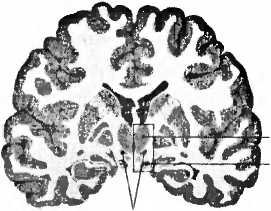

Рис. 22. Пациенту с болезнью Паркинсона имплантирован электрод (Е) в нужное место в субталамическом ядре (nucleus subthalamicus). Т — таламус; ТО — tractus opticus (зрительный тракт).

Если в борьбе с болезнью Паркинсона лекарства оказываются недостаточно эффективными, сейчас довольно часто в мозг больного глубоко имплантируют электрод. Посредством электростимулятора функция небольшой области мозга временно отключается. Поразительно, что, как только сам пациент включает стимулятор, сильное дрожание сразу же прекращается. Эпизод, который привел к использованию электродов глубокого погружения, был нечаянной находкой. В медицине часто бывает, что опытный врач случайно открывает то, чего он совсем не искал. В 1952 году пациенту с болезнью Паркинсона планировалась очень сложная операция на мозге с целью устранения исключительно сильного дрожания ну-тем перерезания моторных путей, что могло в итоге привести к обездвижению больного. В ходе операции хирург Ирвинг С. Купер по оплошности повредил кровеносный сосуд. Кровотечение было остановлено перевязкой сосуда, и операция была прервана по соображениям безопасности. Ко всеобщему удивлению, после неудачной операции тремор совершенно исчез, а об обездвижении и речи не было. После этого Купер уже намеренно прижигал этот кровеносный сосуд, вследствие чего выключалась маленькая область мозга. Ему удалось уменьшить тремор у 65 % больных паркинсонизмом и у 75 % больных скованность мышц. Затем последовал период, когда на основании теоретических предположений выключались различные небольшие области мозга. Выяснилось, что наиболее эффективным является метод, когда выключается область под таламусом, nucleus subthalamicus (субталамическое ядро, рис. 22). Сейчас в большинстве случаев сюда вводят электроды больным паркинсонизмом. Преимуществом метода является возможность самому включать и выключать электрод, оценивая при этом, что именно дает наибольший эффект, и таким образом управлять стимуляцией этой области мозга. Становится возможно положительно воздействовать на вялость или на скованность мышц, на тремор или ходьбу, хотя на течение самой болезни это никак не влияет.

В настоящее время в мире примерно 35 000 человек живут с имплантированным в мозг электродом. Как во всякой действенной терапии, здесь тоже возможны побочные действия. В процессе социальных контактов с партнером или среди рабочего окружения люди с болезнью Паркинсона, которым имплантирован электрод, могут сталкиваться с затруднениями. Хотя большинство пациентов были очень довольны качеством своей жизни, их семьи сообщали, что иногда они делались более возбудимыми и эмоционально неустойчивыми. У 9 % были отмечены психические осложнения: повышенная импульсивность при принятии решений или приступы плача. Стимуляция электродом может усиливать депрессию, а иногда даже приводить к самоубийству. Нам известны пациенты, у которых электроды находились в нужном месте субталамического ядра (рис. 22) и которые пытались совершить самоубийство. Десять лет тому назад неврология еще не проявляла интереса к этой взаимосвязи. Бывает, что имплантация электрода приводит к кровотечению или повреждению мозга, после чего отмечаются проявления деменции, которые исчезают, если стимулятор по-другому отрегулировать. Есть также сведения о возникновении психозов, сексуальной несдержанности и игрозависимости. Пациент, который до операции был типичным бережливым голландцем, после имплантации электрода уже больше не мог спокойно пройти мимо игрового автомата. Лишь после того, как через несколько лет он из-за громадных долгов вынужден был продать дом, его подруга хотела его оставить и он совершил попытку самоубийства, решено было обратиться к врачу. Игрозависимость может возникнуть также при классическом лечении болезни Паркинсона леводопой. Дофаминовая система (рис. 15) играет центральную роль при возникновении зависимостей. Необычное побочное действие наблюдалось у пациента, который стал покупать дома в Испании и Турции, не имея для этого средств; несмотря ни на что, он отказывался отключить стимулятор. Стимуляция глубинными электродами может иногда вызывать нарушения мышления, речи и памяти. Побочные явления психического характера, вызванные глубокой электростимуляцией электродами, всё же в основном преходящи, они хорошо поддаются лечению и их даже возможно предотвращать. Они также дают нам возможность что-то узнать о функции структур и нейронных цепей мозга при симптомах психических заболеваний, как, например, о роли дофаминовой системы при формировании зависимостей. Успех воздействия глубинных электродов при лечении болезни Паркинсона привел к тому, что сейчас их применяют при многих неврологических и психических картинах болезни: невыносимых болях, кластерных головных болях, депрессиях, страхах, мышечных спазмах, самокалечении и обсессивно-компульсивных расстройствах. В ходу исследования лечения ожирения и зависимостей с помощью глубинной имплантации электродов. Возможности приложения этого метода кажутся неисчерпаемыми. Купер о таком и не помышлял, когда в 1952 году по оплошности вызвал кровотечение мозгового сосуда.